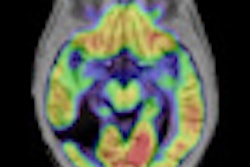

The study describes OCT morphology in nonmelanoma skin cancer (NMSC) lesions during PDT and assesses how OCT morphology before, during, and after treatment reflects the treatment outcome at three-month followup.

The VivoSight scanner uses OCT to provide images of subsurface tissue similar to ultrasound, but at a greater resolution, enabling the clinician to see critical details of the skin epidermis and dermis in real-time.